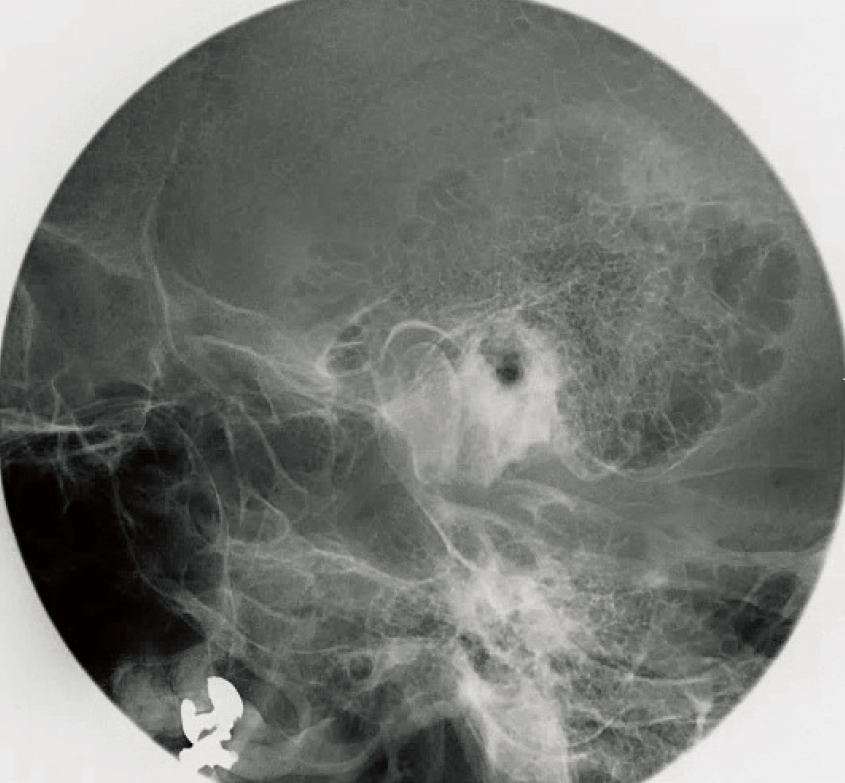

椎体、顔面、頭部の単純撮影法 | 診療放射線技師国家試験 対策ノート。椎体、顔面、頭部の単純撮影法 | 診療放射線技師国家試験 対策ノート。椎体、顔面、頭部の単純撮影法 | 診療放射線技師国家試験 対策ノート。折れや擦れはあります。。足部側面撮影 (立位荷重撮影), Foot lateral view (weight。気になる方はご遠慮ください。歯科矯正メカニクス -その普遍性と臨床応用- Ⅱ